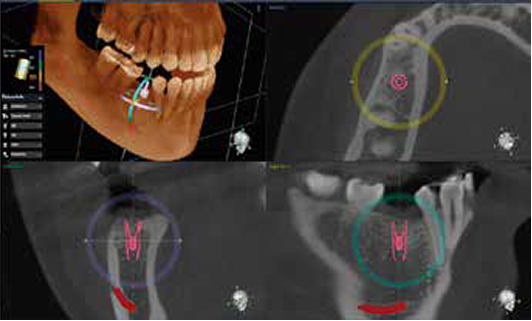

Dentium AI automatically detects the position of the missing teeth and sets the initial position of fixture and crown to minimize implant planning.